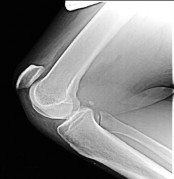

A 45-year-old recreational athlete presents with acute medial knee pain after feeling a 'pop' while deep squatting. MRI demonstrates an extrusion of the medial meniscus of 4 mm and a complete radial tear at the posterior root. Which of the following best describes the primary biomechanical consequence of this specific injury pattern?

A posterior medial meniscus root tear disrupts the circumferential hoop stresses that the intact meniscus relies on to dissipate axial loads. Biomechanical studies demonstrate that a posterior root tear is functionally equivalent to a total meniscectomy in terms of decreasing contact area and dramatically increasing peak tibiofemoral contact pressures, leading to rapid chondrolysis and osteoarthritis if left untreated.